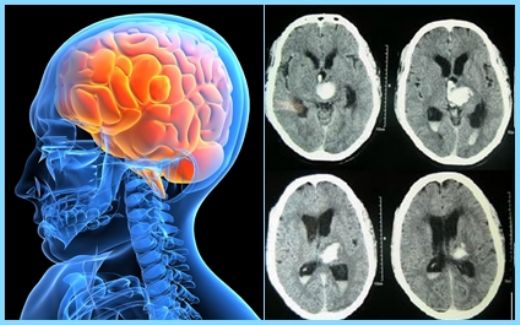

Epidural beyin kanaması, kafatası ile dura mater arasında meydana gelen kanamalardır ve genellikle travma sonucu oluşurlar. Bu tür kanamalar, acil tıbbi müdahale gerektiren ciddi bir durumdur. Bu makalede, epidural beyin kanamasının belirtileri, tanı yöntemleri ve tedavi seçenekleri ele alınacaktır. Epidural Beyin Kanaması Nedir?Epidural beyin kanaması, kafatasının iç yüzeyini kaplayan dura mater tabakasının üstünde, genellikle bir arterin yırtılması sonucunda meydana gelen kanama türüdür. Genellikle travmatik nedenlerle ortaya çıkan bu kanama, hızlı bir şekilde büyüyebilir ve beyin dokusuna baskı yaparak ciddi sonuçlara yol açabilir. BelirtilerEpidural beyin kanamasının belirtileri, kanamanın büyüklüğüne ve yerleşim yerine bağlı olarak değişiklik gösterebilir. Aşağıda, bu durumun en yaygın belirtileri sıralanmıştır:

Bu belirtiler, genellikle kafa travmasından sonra birkaç saat içinde ortaya çıkar ve hızla kötüleşebilir. Tanı YöntemleriEpidural beyin kanamasının tanısı, genellikle aşağıdaki yöntemlerle konulmaktadır:

Bu tanı yöntemleri, epidural kanamanın aciliyetine göre hızlı bir şekilde uygulanmalıdır. Tedavi YöntemleriEpidural beyin kanamasının tedavisi, kanamanın büyüklüğüne ve hastanın durumuna bağlı olarak değişmektedir. Genel olarak tedavi yöntemleri aşağıdaki gibidir:

Epidural Beyin Kanaması: Epidural beyin kanaması, kafatası ve beyin zarlari arasında kan birikmesi durumudur. Bu durumda bilinç kaybı yaşanması sıkça görülür, çünkü kanama beyin üzerinde baskı oluşturur.